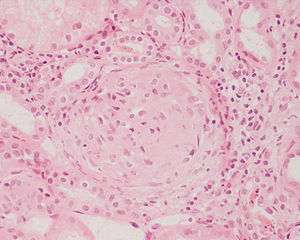

| Photomicrograph of a kidney biopsy from a person with crescentic glomerulonephritis showing prominent fibrocellular crescent formation and moderate mesangial proliferation in a glomerulus. Hematoxylin and eosin stain. | |

Rapidly progressive glomerulonephritis, also known as crescentic GN, is characterised by a rapid, progressive deterioration in kidney function. People with rapidly progressive glomerulonephritis may present with a nephritic syndrome. In management, steroid therapy is sometimes used, although the prognosis remains poor.[6] Three main subtypes are recognised:[4]:557–558

Histopathologically, the majority of glomeruli present "crescents". Formation of crescents is initiated by passage of fibrin into the Bowman space as a result of increased permeability of glomerular basement membrane. Fibrin stimulates the proliferation of endothelial cells of Bowman capsule, and an influx of monocytes. Rapid growing and fibrosis of crescents compresses the capillary loops and decreases the Bowman space, which leads to kidney failure within weeks or months.